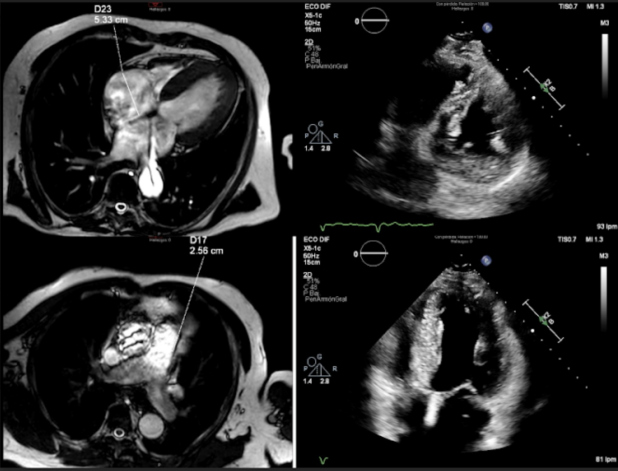

Durante el siguiente año el paciente se mantuvo estable clínicamente, a excepción de episodios aislados de hipertensión. En un nuevo ecocardiograma de control se comprobó una hipertrofia concéntrica severa del ventrículo izquierdo con una función sistólica límite, recomendándose descartar miocardiopatía infiltrativa.

Se realizó una cardio-resonancia magnética (CRM), la cual informó de hallazgos compatibles con miocardiopatía infiltrativa, planteando como primera posibilidad amiloidosis cardíaca (Fig. 1). Finalmente, la gammagrafía con 99mTc-HDP y SPECT/TC torácico reveló captación del radiotrazador por parte de ambos ventrículos, de carácter difuso y grado 3 en la escala de Perugini, siendo estos hallazgos altamente sugestivos de afectación por amiloidosis cardíaca por acúmulo de transtirretina (TTR)(1,2,3) (Fig. 2).